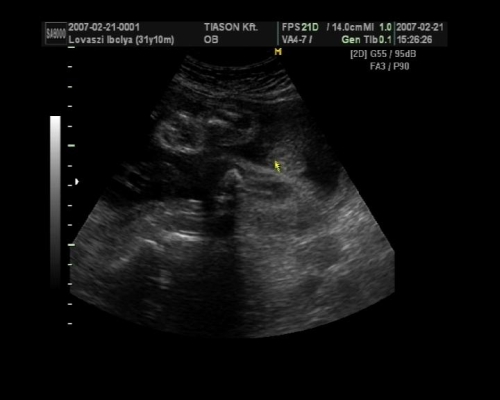

, de ami fura volt, a szívét a pocakom bal oldalán középtájban éreztem, felette pedig folyamatos rugdosást, vagy kalimpálást, De a másik oldalon ugyanott szintén... Lehet, hogy keresztben van???? De a múltkor már lent volt. Na kíváncsi vagyok kedden mit mutat az UH. Dehát azt csak lehetne látni rajtam, ha keresztben lenne...